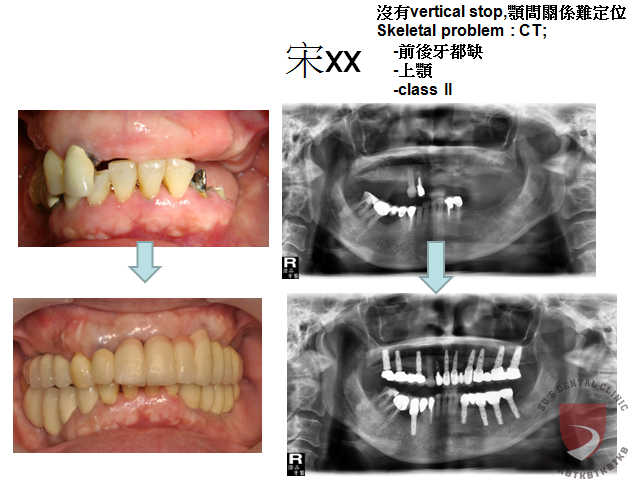

全口重建宋XX

成效因人而異,須遵從專業醫師指引